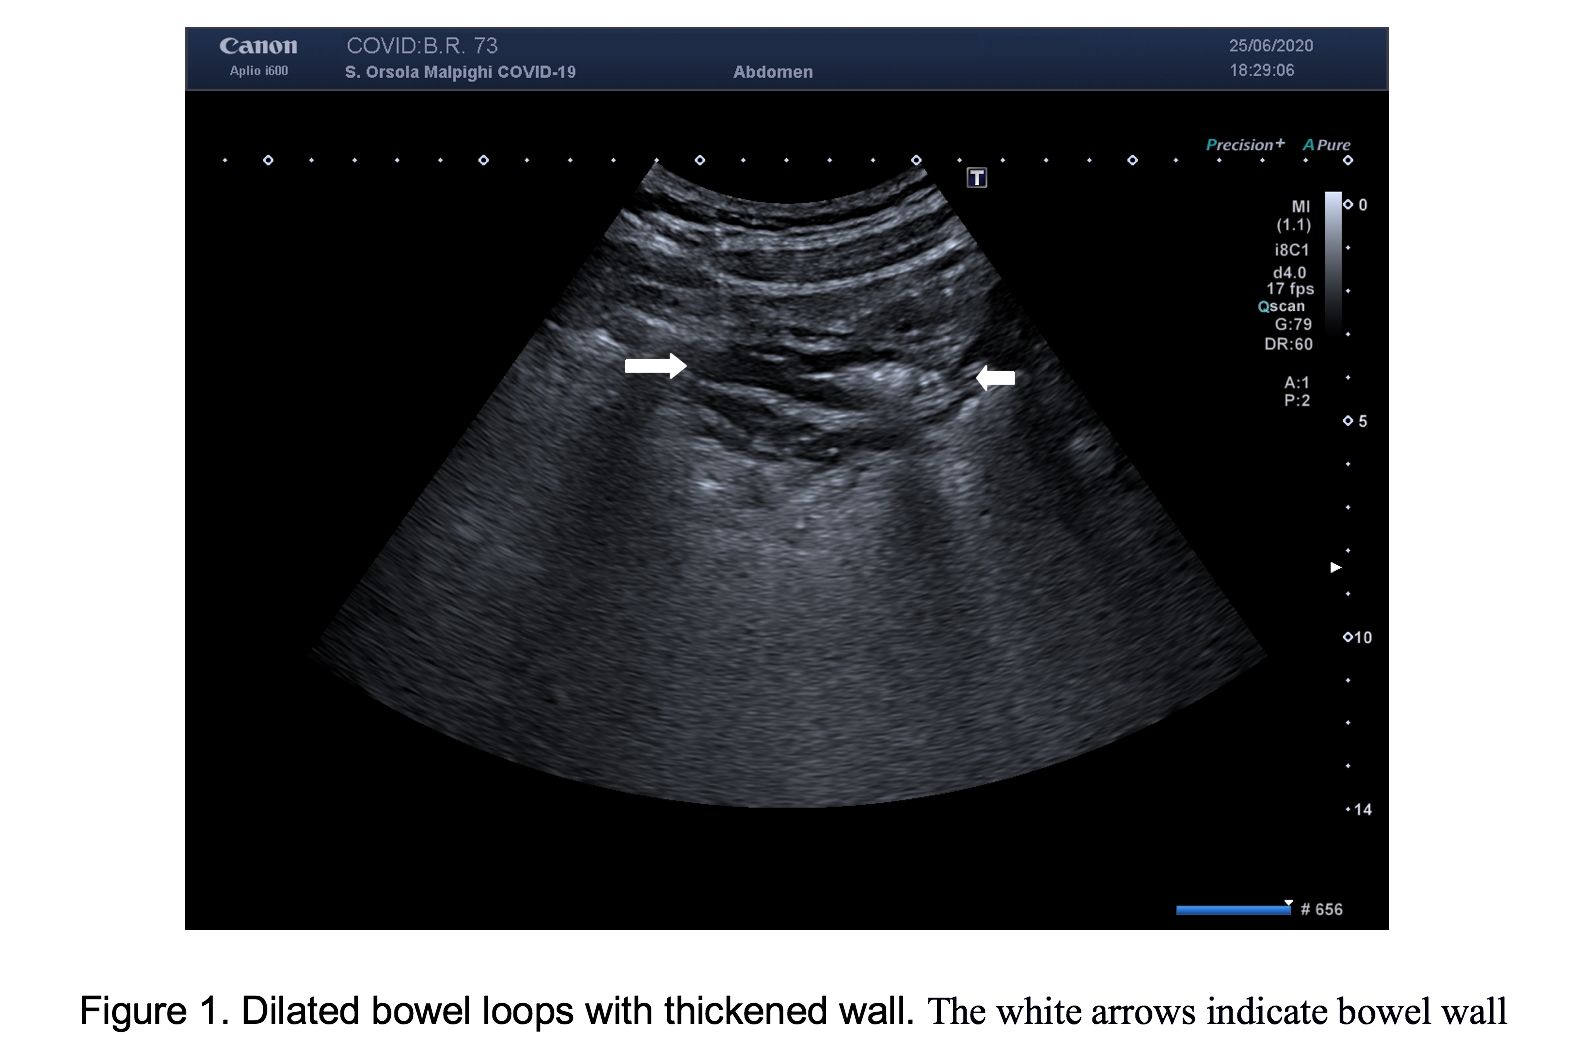

For persistent abdominal pain, we performed bowel ultrasound that showed, in both patients, dilated fluid-filled bowel loops with mildly thickened wall (3-4 mm), in different quadrants of the abdomen (Figure 1). Moreover, the mesenteric root appeared thickened and hyperechoic, with hypo-echogenicity of the adjacent retroperitoneal and meso-colonic fat, with a typical “mass effect” , suggestive of a mesenteritis. The bowel loops and the mesentery root however, did not show increased vascular flow with Colour Doppler and there was no free fluid in the abdomen (Figures 2 & 3; Video 1).

In these two patients, bowel ultrasound showed findings similar to patients with a mesenteritis, suggesting that COVID-19 could also cause inflammation to mesentery with consequent abdominal pain. Further research of patients with COVID-19 and GI symptoms are suggested to confirm these observations and to evaluate the clinical impact of bowel US in this setting.